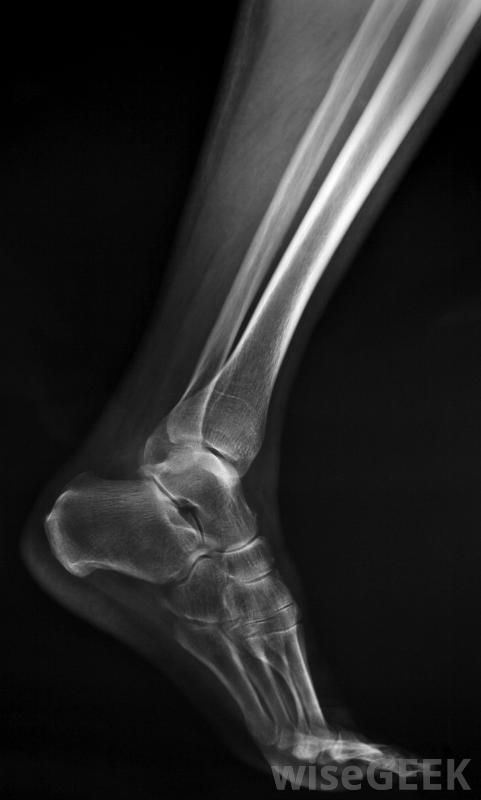

什么問題會影響踝關節軟骨(What Problems Affect Ankle Cartilage)?

踝關節軟骨是人體踝關節內的一種堅韌、柔韌的組織。它提供了一種緩沖作用,防止踝關節摩擦,幫助吸收人體運動時產生的沖擊。有時,這種軟骨可能會因骨折或扭傷等損傷而撕裂或脫離所附著的骨骼,甚至可能會因年齡、運動和重復運動而長期自行磨損。CAT掃描可以幫助醫生查看踝關節的橫截面圖像,以檢查軟骨是否受損。當踝關節軟骨過度磨損時,就會出現一種踝關節疾病,骨骼失去緩沖作用,開始互相摩擦。除了這種不正常的磨擦外,踝關節軟骨的一部分可能會脫離主要部分,進入人的踝關節。這會導致疼痛和炎癥。液體也可能積聚在踝關節的襯里中,導致該區域變硬踝關節的軟骨會撕裂或磨損,引起疼痛踝關節軟骨的磨損不僅對踝關節有問題,還會對身體其他部位造成問題例如,踝關節軟骨的持續磨損會使踝關節內的空間過度狹窄,進而使身體其他關節變得不平衡,最終,一個人的腿和腳甚至可能出現異常,這不僅痛苦,而且會使人虛弱常規的x光檢查對診斷踝關節軟骨損傷可能沒有很大幫助。就像身體其他部位的軟骨一樣,踝關節軟骨可能撕裂。這可能由于該區域的損傷而發生。例如,當腳踝骨折或扭傷時,軟骨可能會撕裂。然而,在沒有明顯損傷的情況下,該區域的軟骨可能會撕裂。事實上,撕裂甚至可能會自發形成當踝關節軟骨過度磨損時,就會出現一種踝關節疾病。與身體其他部位不同,流向踝關節軟骨的血流量通常不足以愈合撕裂。這個部位的軟骨不但不能自行愈合,反而會從環繞它的骨頭上松脫。這會使骨骼相互磨合,游離的軟骨碎片漂浮在踝關節上。結果是踝關節疼痛,該部位腫脹涉及踝關節軟骨的損傷和情況很難用常規的x光片來診斷為了查看和診斷踝關節軟骨損傷,醫生可以使用磁共振成像(MRI),它利用磁場和無線電波對踝關節進行成像。在某些情況下,醫生可能會要求計算機軸向斷層掃描(CAT)來代替或補充MRI。CAT掃描是一種特殊類型的x射線技術允許醫生獲取腳踝的橫截面圖像。當腳踝和身體其他部位的軟骨撕裂時,很難或不可能愈合。